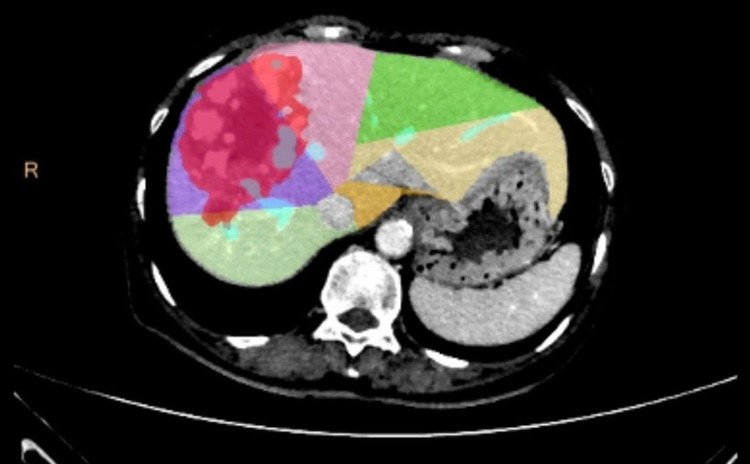

Bệnh nhân là nam giới 48 tuổi, không có tiền sử viêm gan B hoặc C. Người bệnh xuất hiện triệu chứng đau tức vùng bụng trên bên phải, đi khám và phát hiện khối u gan phải kích thước lớn, đường kính 18,6 cm, chiếm gần toàn bộ gan phải.

Tại thời điểm nhập viện vào tháng 7/2025, thể tích gan trái chỉ chiếm 27,1% tổng thể tích gan, chưa đủ an toàn cho phẫu thuật cắt bỏ phần gan phải mang khối u.

Trước tình huống này, các ê kíp chuyên môn đã hội chẩn liên khoa và quyết định thực hiện kỹ thuật can thiệp nút mạch gây tắc tĩnh mạch cửa bên phải (PVE). Thủ thuật này giúp chặn dòng máu nuôi phần gan phải có khối u và đồng thời thúc đẩy phần gan lành bên trái phát triển về thể tích. Chỉ sau 4 tuần, thể tích gan trái tăng lên 36,8% tổng thể tích gan, đủ điều kiện tiến hành phẫu thuật.

cat-gan-2-dg1.jpg

gan-1.jpg

Gan phải và khối u giảm kích, phần gan trái lành phát triển phì đại - Ảnh BVCC